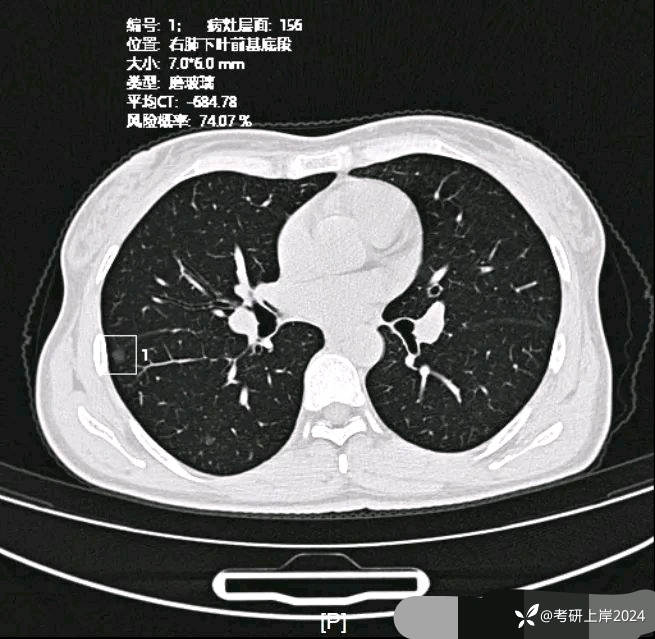

患者最近的检查有AI辅助诊断意见,找出的病灶分别如下:

病灶20:右下叶磨玻璃结节,轮廓清楚,有微小血管进入,瘤肺边界清。考虑原位癌或不典型增生可能性大;

病灶21:右下叶磨玻璃结节,轮廓清,考虑不典型增生可能性较大;

病灶24:右下叶叶裂处结节,实性,边缘光滑,没有收缩力,密度过高,考虑肺内淋巴结或碳沫沉积可能性大。2023年12月最明显的结节形态: